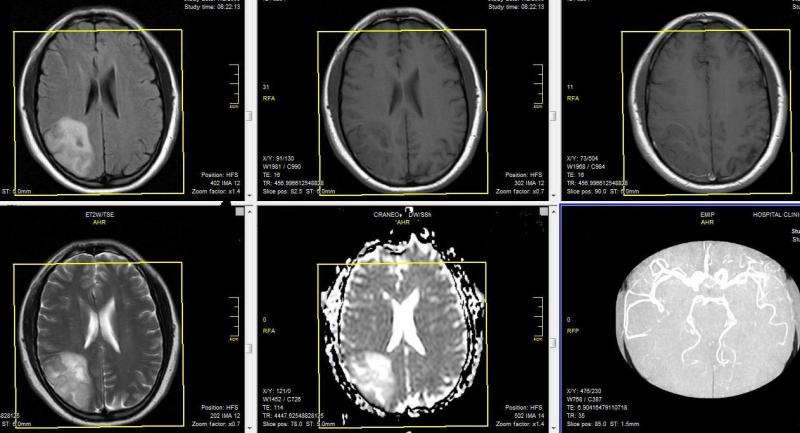

Caso Clínico

Un paciente de 30 años sin antecedentes médicos presenta con una convulsión. Basado en la RMN, ¿Cual es su diagnostico?

A) Infarto Cerebral

B) Trombosis Venosa Cerebral

C) Ruptura de Aneurisma

D) Hemorragia Subarachnoidea

E) Oligodendroglioma

Ver Respuesta en contáctenos.